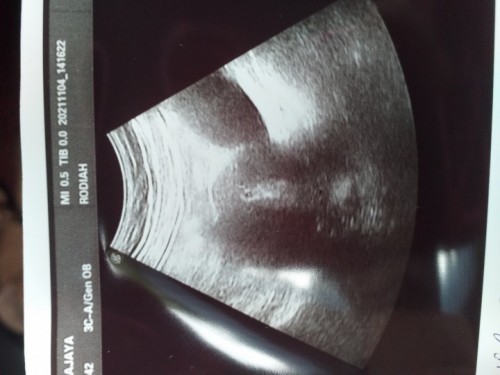

Salam semua, ada ke pernah alami period 2 hari tp heavy, bila saja² buat upt ada samar², sebelum tu period delay sebulan. Bila pergi scan doc kata nampak kantung dlm rahim, tp kecik. Lebih kurang awal 4weeks. Nak tunggu next scan 18/11. Buat upt masih samar sangat² . Masa pergi scan tu nk cek risau ada cyst/fibroid . Tiba² doc kata nampak kantung. Ada tak pernah alami? Bila next scan makin berkembang ke kantung? Kalau betul² pregnant syukur sgt, dah lama menanti. 😔❤